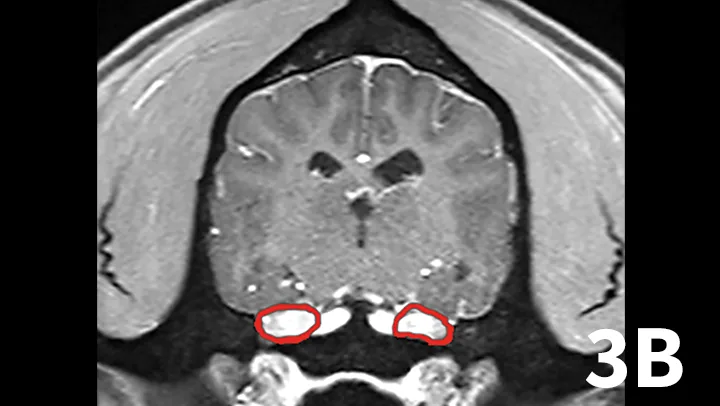

A range of infectious and noninfectious inflammatory diseases can affect peripheral nerve branches. The most frequently recognized inflammatory entity in dogs affecting peripheral branches of cranial nerves is trigeminal neuritis or idiopathic trigeminal neuropathy (ITN).5 Affected dogs typically have an acute onset of clinical signs secondary to bilateral motor branch dysfunction of the trigeminal nerves. This bilateral involvement of the trigeminal nerve results in inability to close the mouth (drop jaw), difficulty prehending food, and drooling.5 About 33% of dogs have sensory involvement of the trigeminal nerve, and <10% have Horner syndrome or facial nerve dysfunction.5 While the underlying pathogenesis of this disease is not known, it is believed to be noninfectious and inflammatory in origin.5 Other causes can be excluded via MRI and cerebrospinal fluid analysis. Reported MRI findings include bilateral, subtle enlargement of the trigeminal nerve with associated T2 hyperintensity (Figure 3).2 The reported mean time to recovery is 22 days with <10% of dogs taking >6 weeks to recover.5 No treatment beyond assisted feeding is recommended for ITN. It may be necessary to try several food consistencies to determine what will be easiest for a particular dog to prehend; rarely, feeding tubes may be necessary. Team members who handle dogs (or cats) with any acute neurologic disease process, especially involving the trigeminal nerves or lower motor neuron system, should wear gloves, as rabies is a differential diagnosis, especially in unvaccinated animals.

Transverse postcontrast T1WI at the level of the caudal thalamus from a normal dog (A) and a dog with trigeminal neuritis (B). The trigeminal nerves are outlined in each study in red. The dog with trigeminal neuritis has grossly enlarged trigeminal nerves without an overt, identifiable mass.